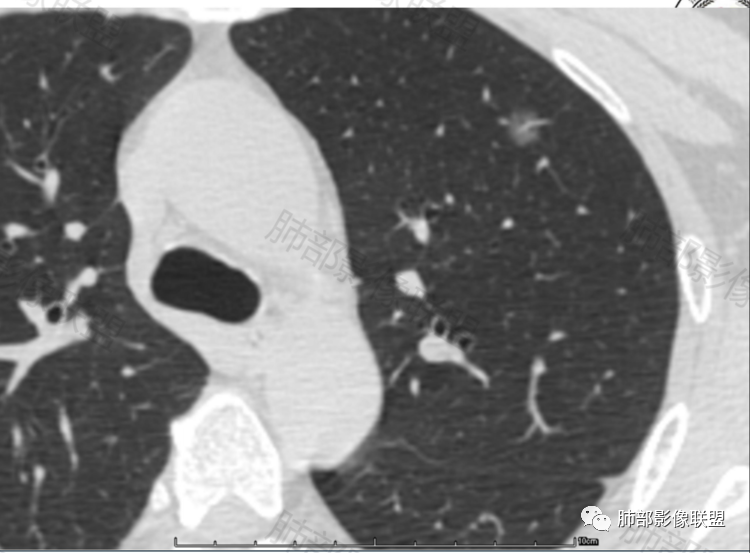

晨读,病例一:左肺磨玻璃结节,边缘清楚,内部有血管穿行自然,有低密度空泡?支气管?10个月后复查,结节增大0.2CM,不排除误差,考虑良性结节或炎性结节,继续短期随访。

病历二:左肺磨玻璃结节影,边界清楚,内部血管穿行,考虑炎性结节或良性结节,继续短期随访。

这两个病例都是偶发肺内孤立结节,以磨玻璃密度为主,无明显实性成分,边界清晰,并且都经过长期(10-14个月)随访复查,病灶整体大小、形态、密度变化不明显。

两例最终都选择了手术,病例1结果:局灶性肺纤维化;病例2结果:浸润性肺腺癌。

由此可见,随访持续存在的磨玻璃结节,并不一定都是早期肺腺癌(AIS MIA IAC)或癌前病变(AAH),也可以是局灶性肺纤维化或机化。影像学表现缺乏特异性,有时候并不能完全鉴别。